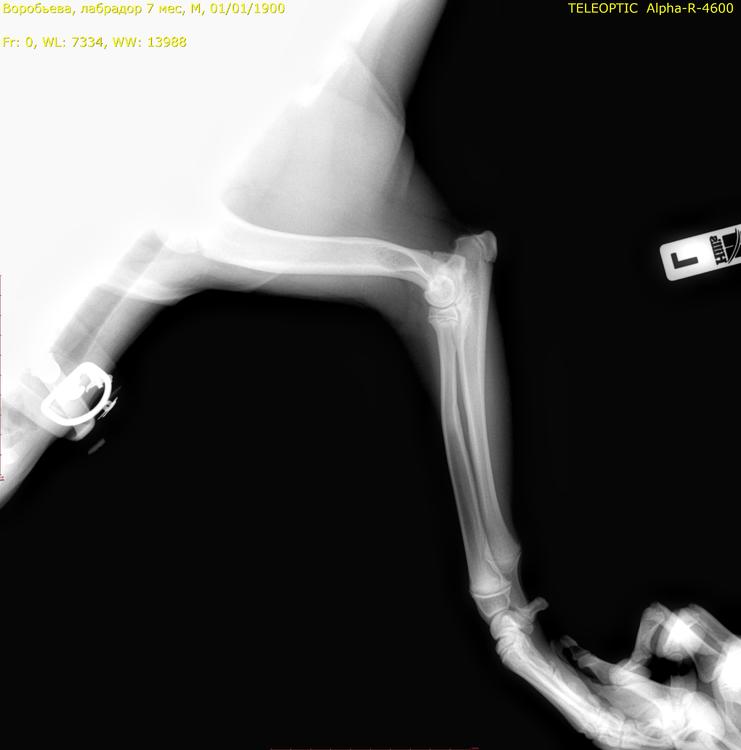

сделали рентген, ничего не нашли. но собака хромает. день сильно хромает день слабо. потом вообще не хромает, может долго не хромать. прошло полторы недели она побегала сильно и снова начала лапа сильно хромать передняя. дали таблетки превикокс, сказали если через неделю опять будет хромать, то возможно дисплазия и надо будет делать артроскопию или компьютерную томографию. я не знаю что это может быть. снимки ниже - но не все уместились9999_00015491.jpg.445e6e663116dbc373a10d9bc5e488da.jpg9999_00015492.jpg.1483c792e930011ebb0e20b405812211.jpg

Начальная стадия может быть не видна на рентгене, при этом есть периодическая хромота. Не давайте скакать и беситься строго. Нельзя играть с собаками. Шаг и спокойная рысь на поводке до постановки точного диагноза.